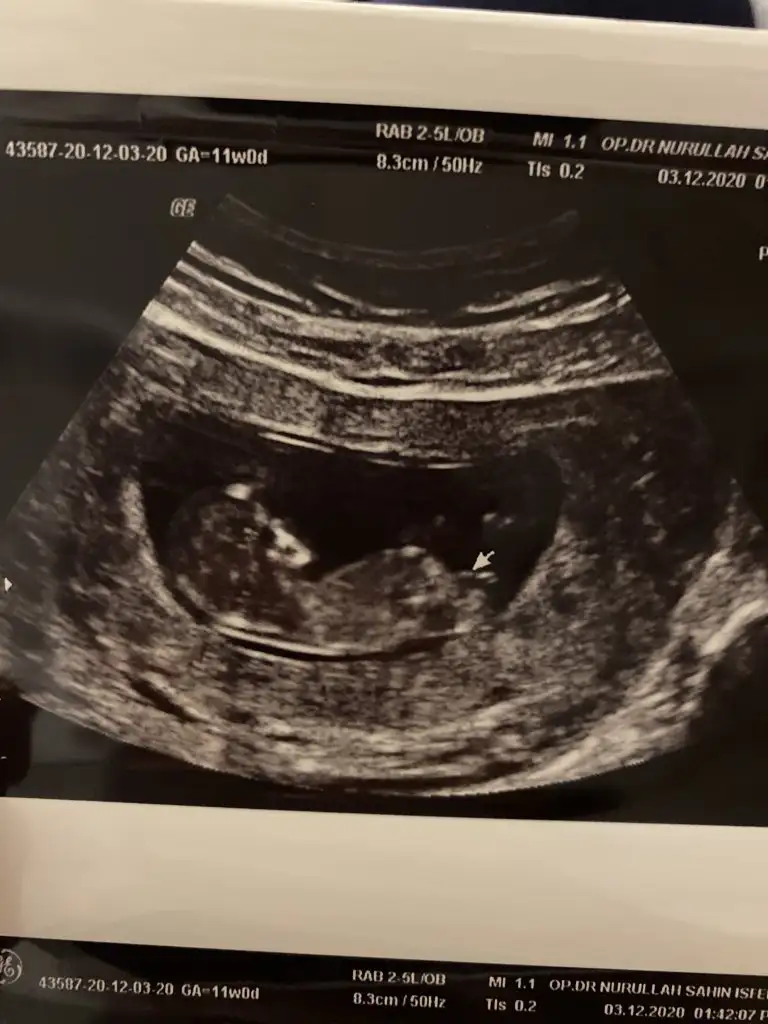

Kizlar Bi baka bilirmisiniz kiz bebeginde bacak arasinda bu cikinti oluyomu ?

Kız gibi sanki yinede 12+13 olursa paylaşın emin olamadım

Emin olamadım sanki kız gibi gibi 12+13 haftalarda paylasin